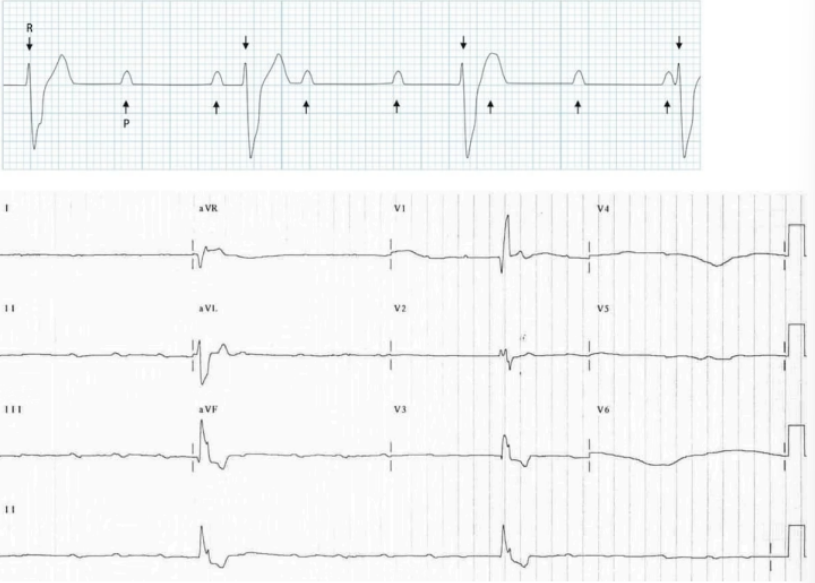

What is seen in third degree AV block

P and QRS complexes are independent

What does this indicate

P and QRS are independent → Third degree AV block